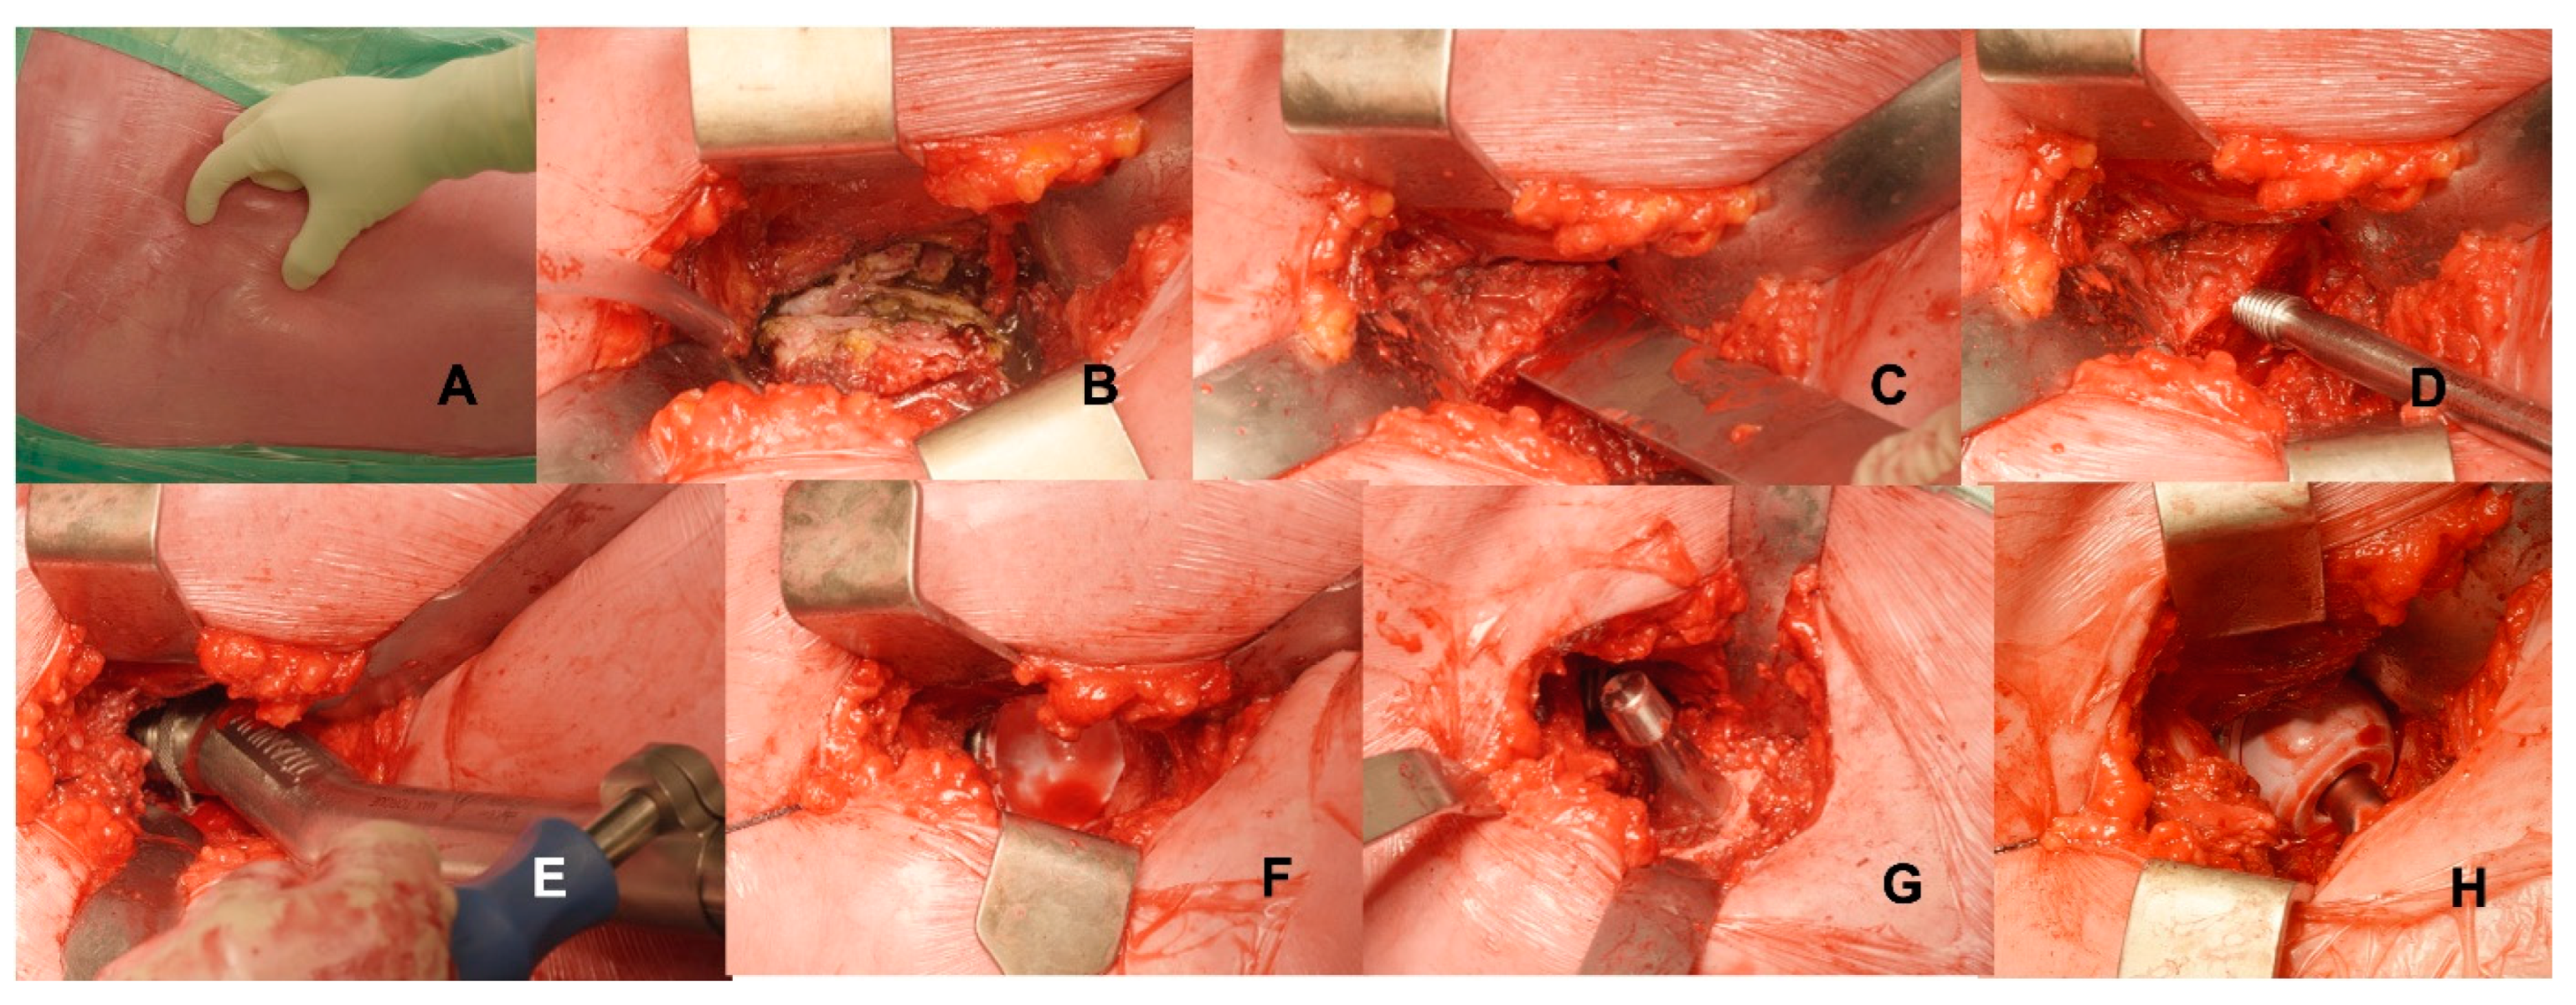

2.1. Surgical Technique